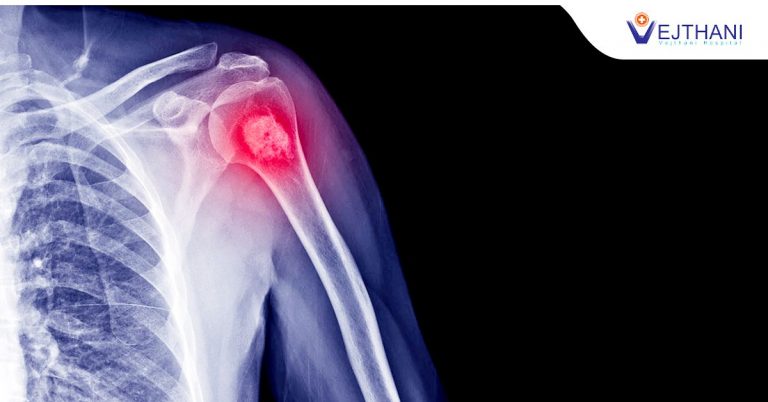

Bone Cancer

Knowing the symptoms of bone cancer can save your life. Although bone cancer is fairly rare, it can be debilitating if not caught in time. Knowing the symptoms of bone cancer can make your survival and ultimate recovery from the disease more likely. Knowing the symptoms of bone cancer can save your life. Although bone […]